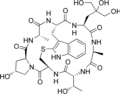

Phallacin Phallisacin

Phallisacin